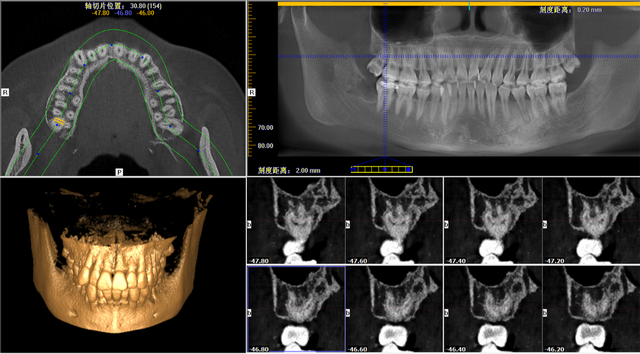

拔牙之前,傅呂通過(guò)口腔CT,告知明女士右邊上面智齒爛的很深,需盡快拔除。不僅如此,口腔CT還提示明女士該智齒有四個(gè)又彎又細(xì)的牙根,牙根離上頜竇非常近,斷根及斷根掉落上頜竇的風(fēng)險(xiǎn)較大,完整拔出來(lái)難度很大。

明女士口腔CT圖